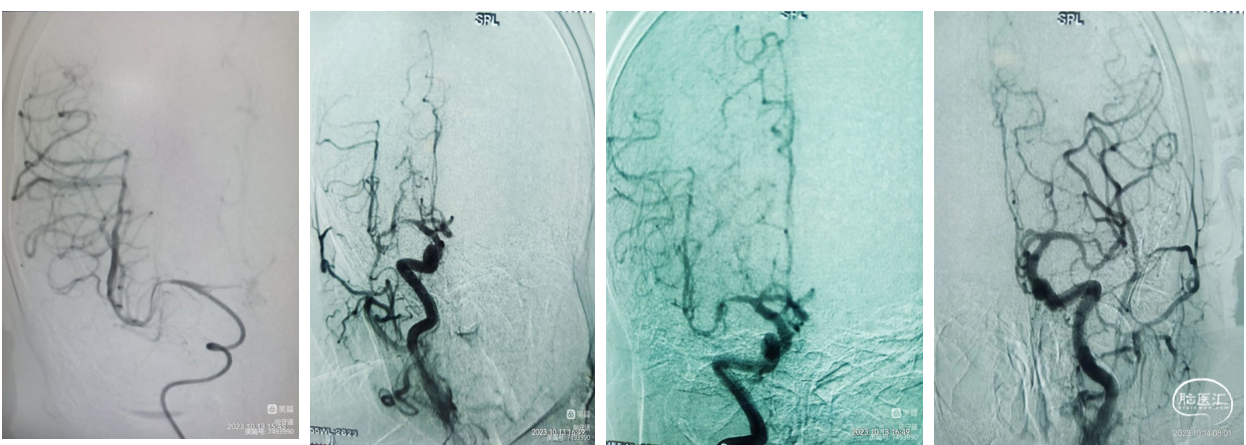

现病史:患者于2小时前突发言语含糊,吐字不清,头晕、头昏,左侧上下肢无力。患者之女自驾车送来我院就诊。既往史:有高血压病史5年余,2年前患右侧基底节区脑梗死经治疗好转,无明显后遗症。专科查体: 意识清,言语含糊,左侧上下肢肌力3级。左侧巴宾斯基(++),NiHSS评分7分。辅助检查:核磁DWI显示:右侧基底节区多发点状梗塞灶,考虑低灌注。MRA显示:右侧大脑中动脉M1段以远端未显影,考虑ICAS病变。

治疗过程影像简述:

导丝携带微导管到达M1段,跟进天巡5F中间导管通过眼动脉段到达M1段。路图下下微导丝到达M2段,跟进微导管,反复来回抽拉微导管捣栓、碎栓。

术中影像简述:

术中造影显示:远端血管再通,推注替罗非班20mL。再次造影显示:M1分叉部狭窄,但血流达到3级,远端显影良好。M1分叉部血管成角明显,球囊扩张可能出现夹层或血管撕裂,血管已达到3级再通,遵循"有所为,有所不为",无置入理念。

患者术后情况:

术后患者意识清,生命体征正常,血压125/80mmHg,言语流畅,肢体肌力5级,病情明显递转,可自行端碗吃饭和肢体活动。